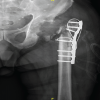

A 76 year old with a BMI of 36 kg/m2 male presented to the Emergency Department with left-sided hip pain and discomfort after performing a “twisting” motion of his hip while getting into bed. He described a “popping” sensation in his left hip upon doing this movement and immediately experienced a sharp pain and was unable to weight bear on that side. The patient described a discomfort in that left hip for the last 4 weeks before this acute presentation, which was not triggered by any trauma/injury. This patient had a MoM THA that was performed 16 years ago for osteoarthritis. He had had a successful outcome until now and denied any post-operative complications after the procedure. The MITCH TRH Modular head with an Exeter V40 cemented stem was used and the operation performed by an experienced consultant orthopedic surgeon. The patient’s medical history includes atrial fibrillation, coronary stenting, high BMI (36 kg/m2) hypertension, hypercholesterolemia, and bilateral total knee replacements. The patient is a non-smoker with occasional alcohol intake and mobilizes independently without walking aids at baseline. Clinical examination at the presentation revealed a shortened limb on the left side held in the neutral position. The patient was unable to straight leg raise due to pain and had a normal neurological and vascular examination. No visible signs of injury or trauma were present, and a systems examination was normal. The patient was admitted under the care of the orthopedic team, and investigations, including X-rays, MARS scan, laboratory tests (Full blood count, renal profile, C-reactive protein, coagulation profile, metal ion levels), and electrocardiogram, were ordered. X-rays (Figs. 1 and 2) revealed head-stem dissociation in a MoM hip configuration. Blood investigations were within normal levels and without any evidence of infection. Of note, metal ion levels are still in process. A MARS scan was conducted which revealed a subfascial 7cm × 7 cm × 10 cm collection posterior to the THA (Fig. 3.)

The surgical wound was closed in layers in a standard fashion with PDS sutures and skin clips. Following a confirmation of negative tissue samples and cultures swabs from the microbiology laboratories, opinion was sought from the infectious diseases team regarding 2nd stage revision. Given that the patient had negative culture swabs and pre-operative inflammatory markers were normal, decision was made to proceed with early 2nd stage revision 1 week after the 1st stage procedure. The same surgical incision was used to regain access to the hip joint. The cement spacer was removed and the final components (cemented Exeter v40 stem size 1 with 50 mm offset, 36 mm standard ceramic head, 58 mm Trident Hemispherical Uncemented cup with 36 mm 10° eccentric insert) were implanted (Fig. 6). The hip was stable in all ranges of motion, and leg lengths were equal. The surgical wound was closed again in a similar fashion to the 1st stage procedure with PDS sutures and skin clips.